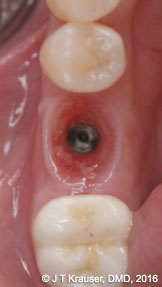

Figure 3 presents the occlusal view of a modern design Megagen AnyRidge® implant with its early maintenance of the buccolingual ridge form. In other words, the buccal frenum pull was prophylactically released to alleviate tissue tension and lower the risk of marginal tissue recession in the future. Figure 3 clearly demonstrates healthy gingival mucosa in the absence of any frenum pulls or tension.